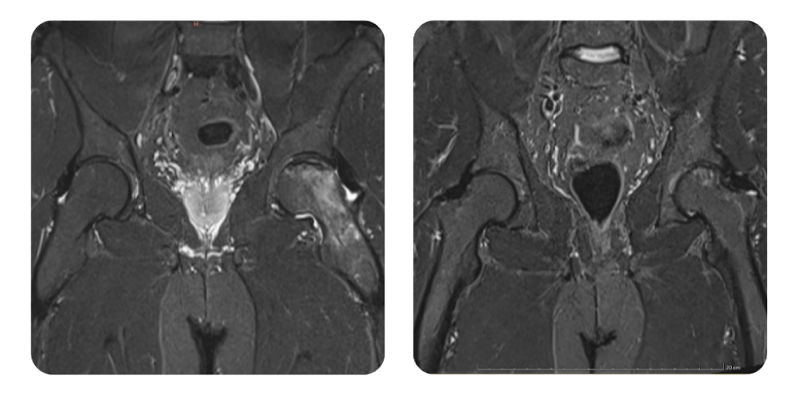

Prima

Dopo

T.K., 41 anni - Necrosi avascolare della testa femorale sinistra, stadio 2/3

Diagnosi: Necrosi avascolare della testa femorale sinistra, stadio 2/3.

Evoluzione: Dopo 2 mesi il paziente si presenta a rivalutazione: soggettivamente il dolore si e ridotto da 7-8/10 a 2-3/10 e, all'imaging, l'edema osseo si e ridotto di circa il 40%; il paziente e soddisfatto e desidera proseguire la terapia.

Dopo ulteriori 40 sedute di HBOT, il paziente si presenta a rivalutazione con RMN a un anno e riferisce scomparsa del dolore, presente solo con freddo e movimenti ampi; inizialmente il dolore era 7-8/10 e la mobilizzazione avveniva solo con stampella.

Guarigione quasi completa (remissione di circa il 100%). Si raccomandano sedute di mantenimento solo al bisogno.